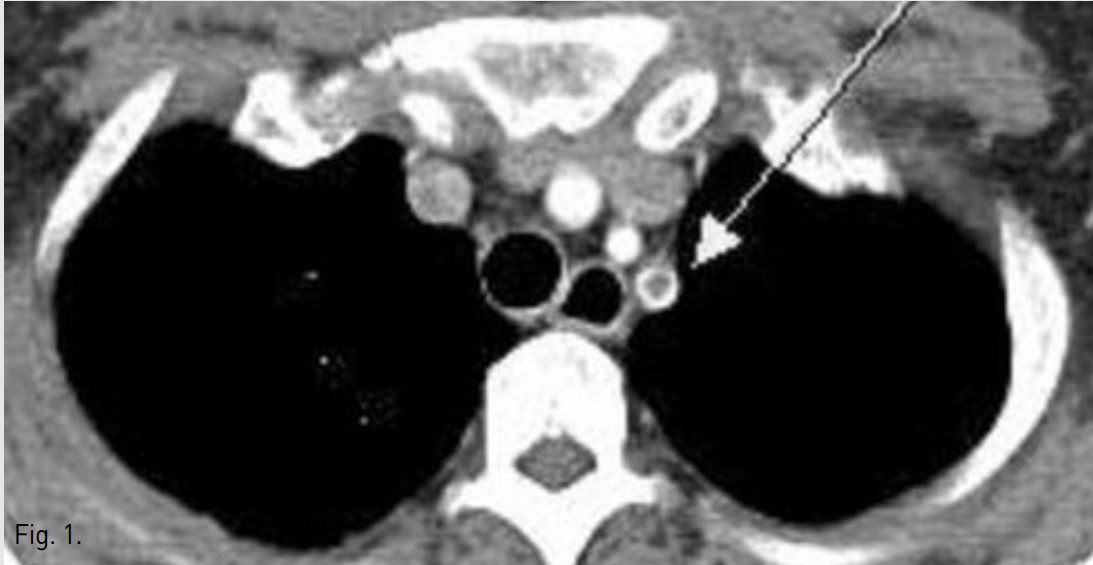

입원 3일 후 시행한 상지 CT 소견 상 left subclavian artery의 기시부에 약 3cm 길이의 thrombus가 보이며, 이 혈전은 aortic arch로 약 0.5cm 이상 튀어나와 있는 형태를 보였음(Fig. 1). 그리고 left radial artery와 left ulnar artery에도 thromboemboli가있음 (Fig. 2).

Fig. 2.

CT scan revealed 3cm sized partial thrombusprotruding into the aortic arch in origin of the left subclavian artery on axial(1, arrow) and sagittal scan (2).